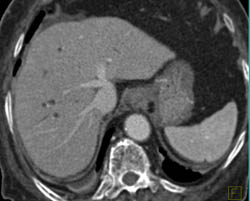

Cholangiocarcinoma of the Distal Common Bile Duct (CBD) Which Is Enhancing- See Full Sequence